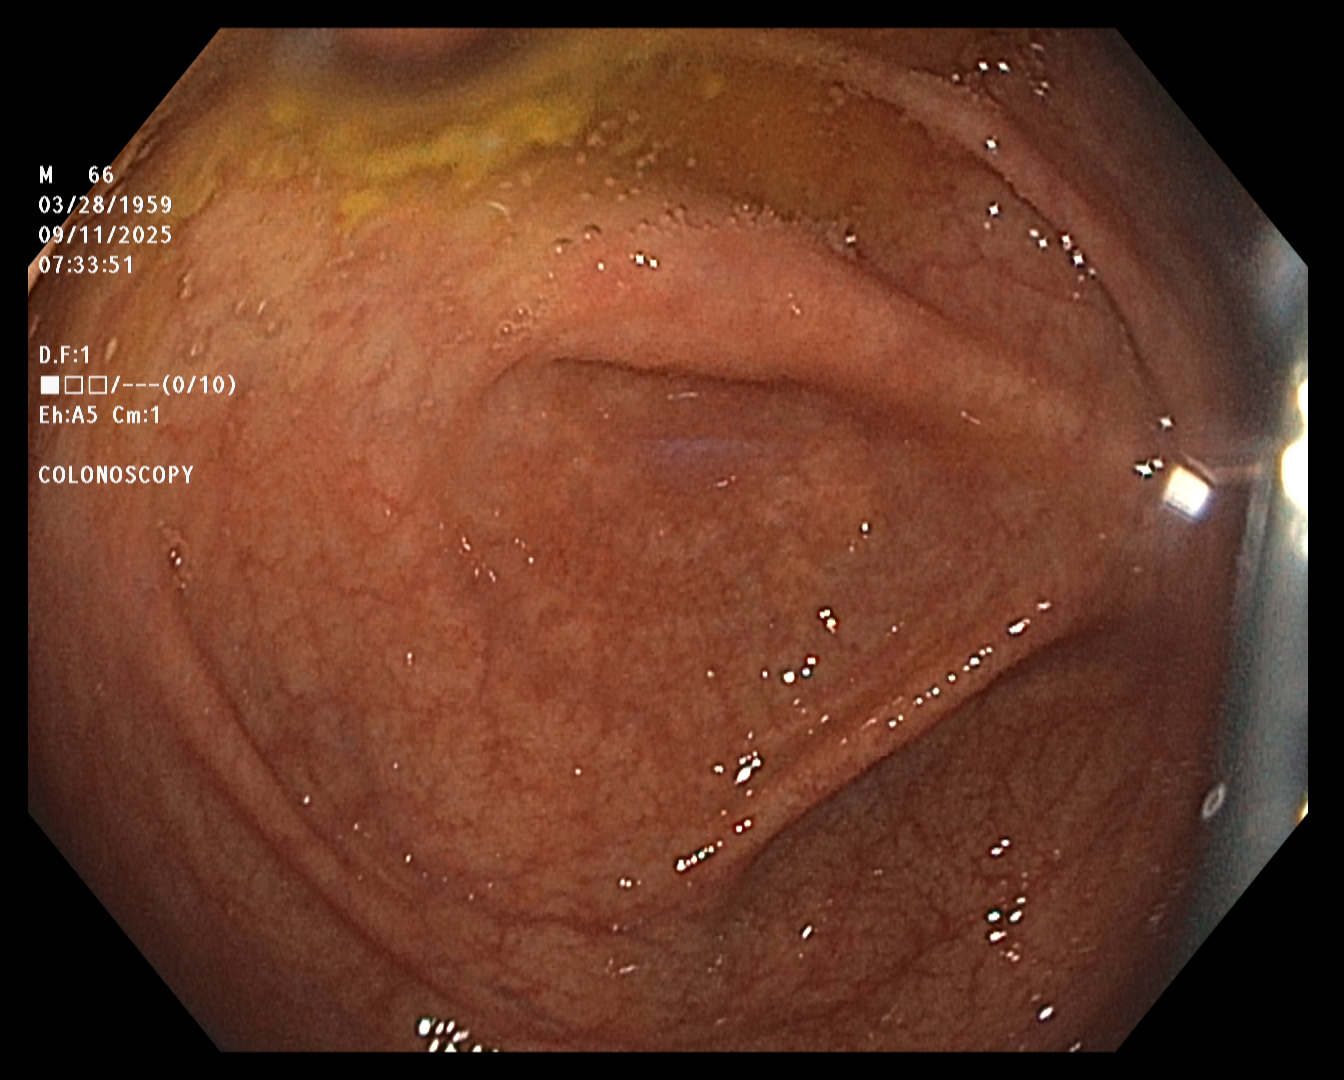

The endoscopist in this study generated a series of images showing the cecum and several sites

of concern (e.g., polyps). The cecum is the beginning of the colon, so reaching it ensures that

the entire colon will be examined. The endoscope was slowly withdrawn, while the endoscopist

assayed mucosal detail and identified and removed several polyps for later examination. The

first and last images were taken about twenty minutes apart.

The colonoscopy results were relatively unconcerning. However, because polyps were

detected, the patient was advised to repeat the procedure in five years.

Polyp 1